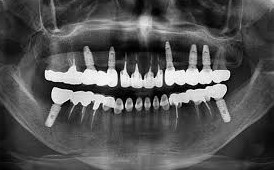

5. 보험 적용되는 재료와 범위는?

2025년부터는 지르코니아 보철(심미성 우수)도 선택 가능하여, 앞니에도 자연스러운 결과를 얻을 수 있습니다. 적용 부위는 앞니, 어금니 관계없이 전 치아에 가능합니다. 그러나 보철물 변경 비용, 치조골 이식 등은 비급여로 따로 부담해야 합니다.